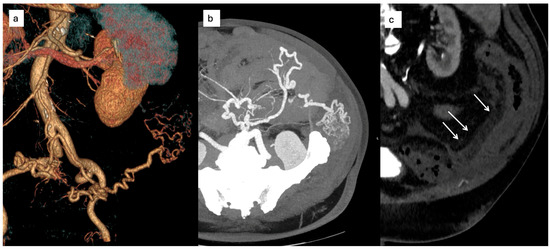

Background/Objectives: Endoscopic biliary stenting is the standard palliative intervention for malignant biliary obstruction, aimed at restoring ductal patency. Radiofrequency ablation (RFA) has been introduced as an adjunct technique to improve stent durability and patient outcomes. However, the literature remains inconclusive regarding which patients are most likely to benefit from the combination of RFA and stenting. Methods: We retrospectively described clinical outcomes of 24 patients undergoing endobiliary RFA combined with biliary stenting for malignant biliary obstruction. Post-procedural and 6-month outcomes were assessed using technical success and changes in serum bilirubin; procedure-related adverse events were extracted from available medical records. Results: Nineteen females and five males were included in the study. The most prevalent diagnoses were metastatic adenocarcinoma (n = 8) and cholangiocarcinoma (n = 6). 25% of patients did not complete the 6-month follow-up due to malignancy progression. 16 out of 18 maintained the patency of biliary stents. Repeat endoscopic intervention for suspected stent dysfunction was documented in one patient. When analyzed in an intention-to-treat manner (counting deaths before 6 months as failures), the corresponding 6-month patency/clinical success rate was 16/24 (66.7%). Conclusions: In this retrospective single-center experience, RFA combined with biliary stenting was feasible and was associated with maintained biliary drainage in a majority of patients who survived to the 6-month assessment.